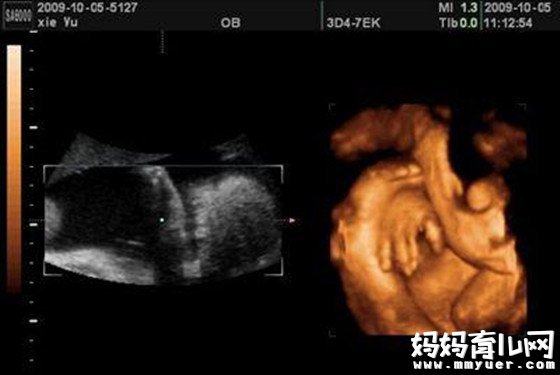

怀孕七个月胎儿图

怀孕七个月胎儿图什么样?

七个月胎儿已经开始有了呼吸动作,尽管他们的肺叶还没有发育成熟,但这不妨碍他们有自己的一套小乐趣,有时候您可以从彩超上看到孩子把手指放到嘴巴里去吮吸呢。他们的四肢也已经发展的十分灵活,经常可以看见他们在羊水中手脚并用的玩耍呢。